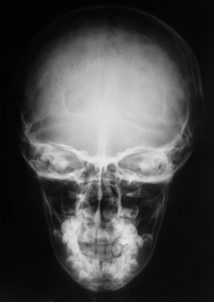

O que pode ser bem visualizado no Rx AP/PA?

Região frontal e órbitas. Se o Rx for bem feito pode-se visualizar estruturas do ouvido interno dentro das órbitas.

Sutura Sagital, Sutura Occipital, Órbitas, Septo Nasal, Cavidades Nasais